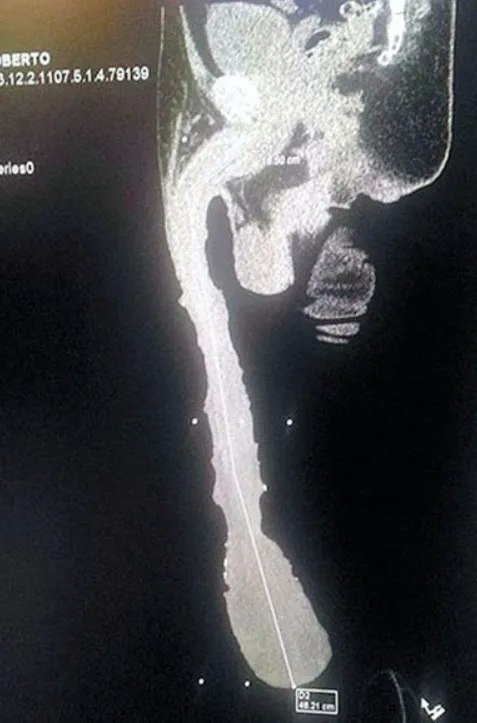

PinkNews cho biết một bác sĩ X quang đã kiểm tra Cabrera và ********* của anh ấy thực sự dài khoảng 15cm. Bác sĩ Munro cho biết: “Kết quả CT cho thấy Cabrera có một bao quy đầu rất lớn. Nó dài tới tận đầu gối. Nhưng bản thân ********* chỉ dài khoảng 16-18cm”.

Đó cũng là lý do nhiều chuyên gia kiểm tra cho Cabrera tin rằng, phần lớn kích thước ********* của anh chỉ là phần thịt của bao quy đầu.

Roberto Esquivel Cabrera, 54 tuổi đến từ Saltillo, Mexico là một người đàn ông có ********* khủng. Với kích thước 48cm, Cabrera được cho là người có ********* lớn nhất thế giới và anh hy vọng sẽ được sách kỷ lục Guinness công nhận.Anh đã gây chú ý vào năm 2015 sau khi một video quay cảnh anh ấy đo độ dài của ********* được lan truyền.

Hiện tại Cabrera vẫn chưa được thêm vào sách kỷ lục Guinness thế giới vì chiều dài trên được do từ bao quy đầu kéo dài của anh ấy chứ không phải chính trục.Cabrera nói với Barcroft TV: “Tôi nổi tiếng vì tôi có ********* lớn nhất thế giới. Tôi hài lòng với ********* của mình, tôi biết không ai có kích thước như tôi. Tôi muốn được ghi vào sách kỷ lục Guinness nhưng họ không công nhận điều này và họ không chấp nhận”.